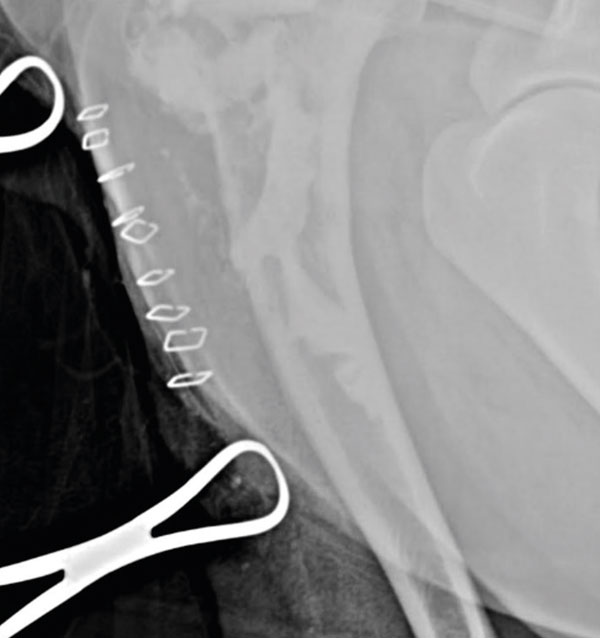

The surgery site was then thoroughly lavaged, the wound was routinely closed, and post-operative x-rays were taken to assess the degree of filling of the lesion (Figure 6). Contact between the bone substitute and intact surrounding cortical bone is recommended for a positive outcome, along with maximal filling of the defect. Calcium-phosphate bone substitute is expected to achieve a mechanical strength comparable to cancellous bone within the first 24 hours post-operatively.12 When available, fluoroscopy is a valuable option for real-time monitoring of percutaneous injections.

Figure 6.